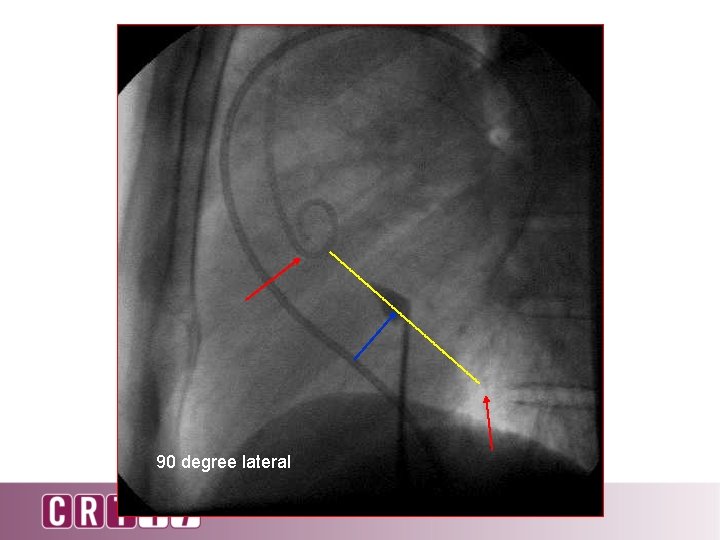

90 o lateral

90 degree lateral